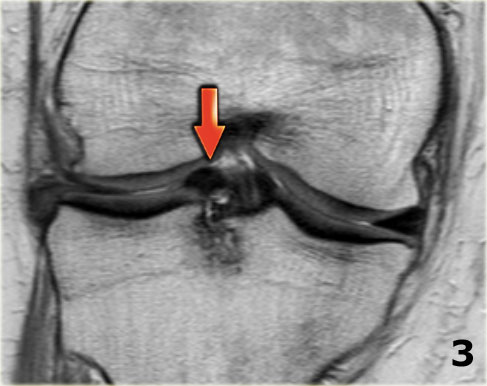

Trên hình ảnh mặt phẳng coronal, trước tiên sẽ thấy sừng trước to và phồng lên.

Ở phía sau sẽ thấy sừng sau rất nhỏ.

- Lưu ý sừng trước rất lớn.

Phần trong là sừng sau đã bị di lệch. - Phần trong chạy vào hố gian lồi cầu.

- Phần bị di lệch được nhìn thấy rõ ràng như là ‘cấu trúc thứ ba’

trong hố gian lồi cầu. - Điểm nối với phần còn lại của sừng sau.

- Điểm nối với phần còn lại của sừng sau.

- Phần còn lại rất nhỏ của sừng sau.